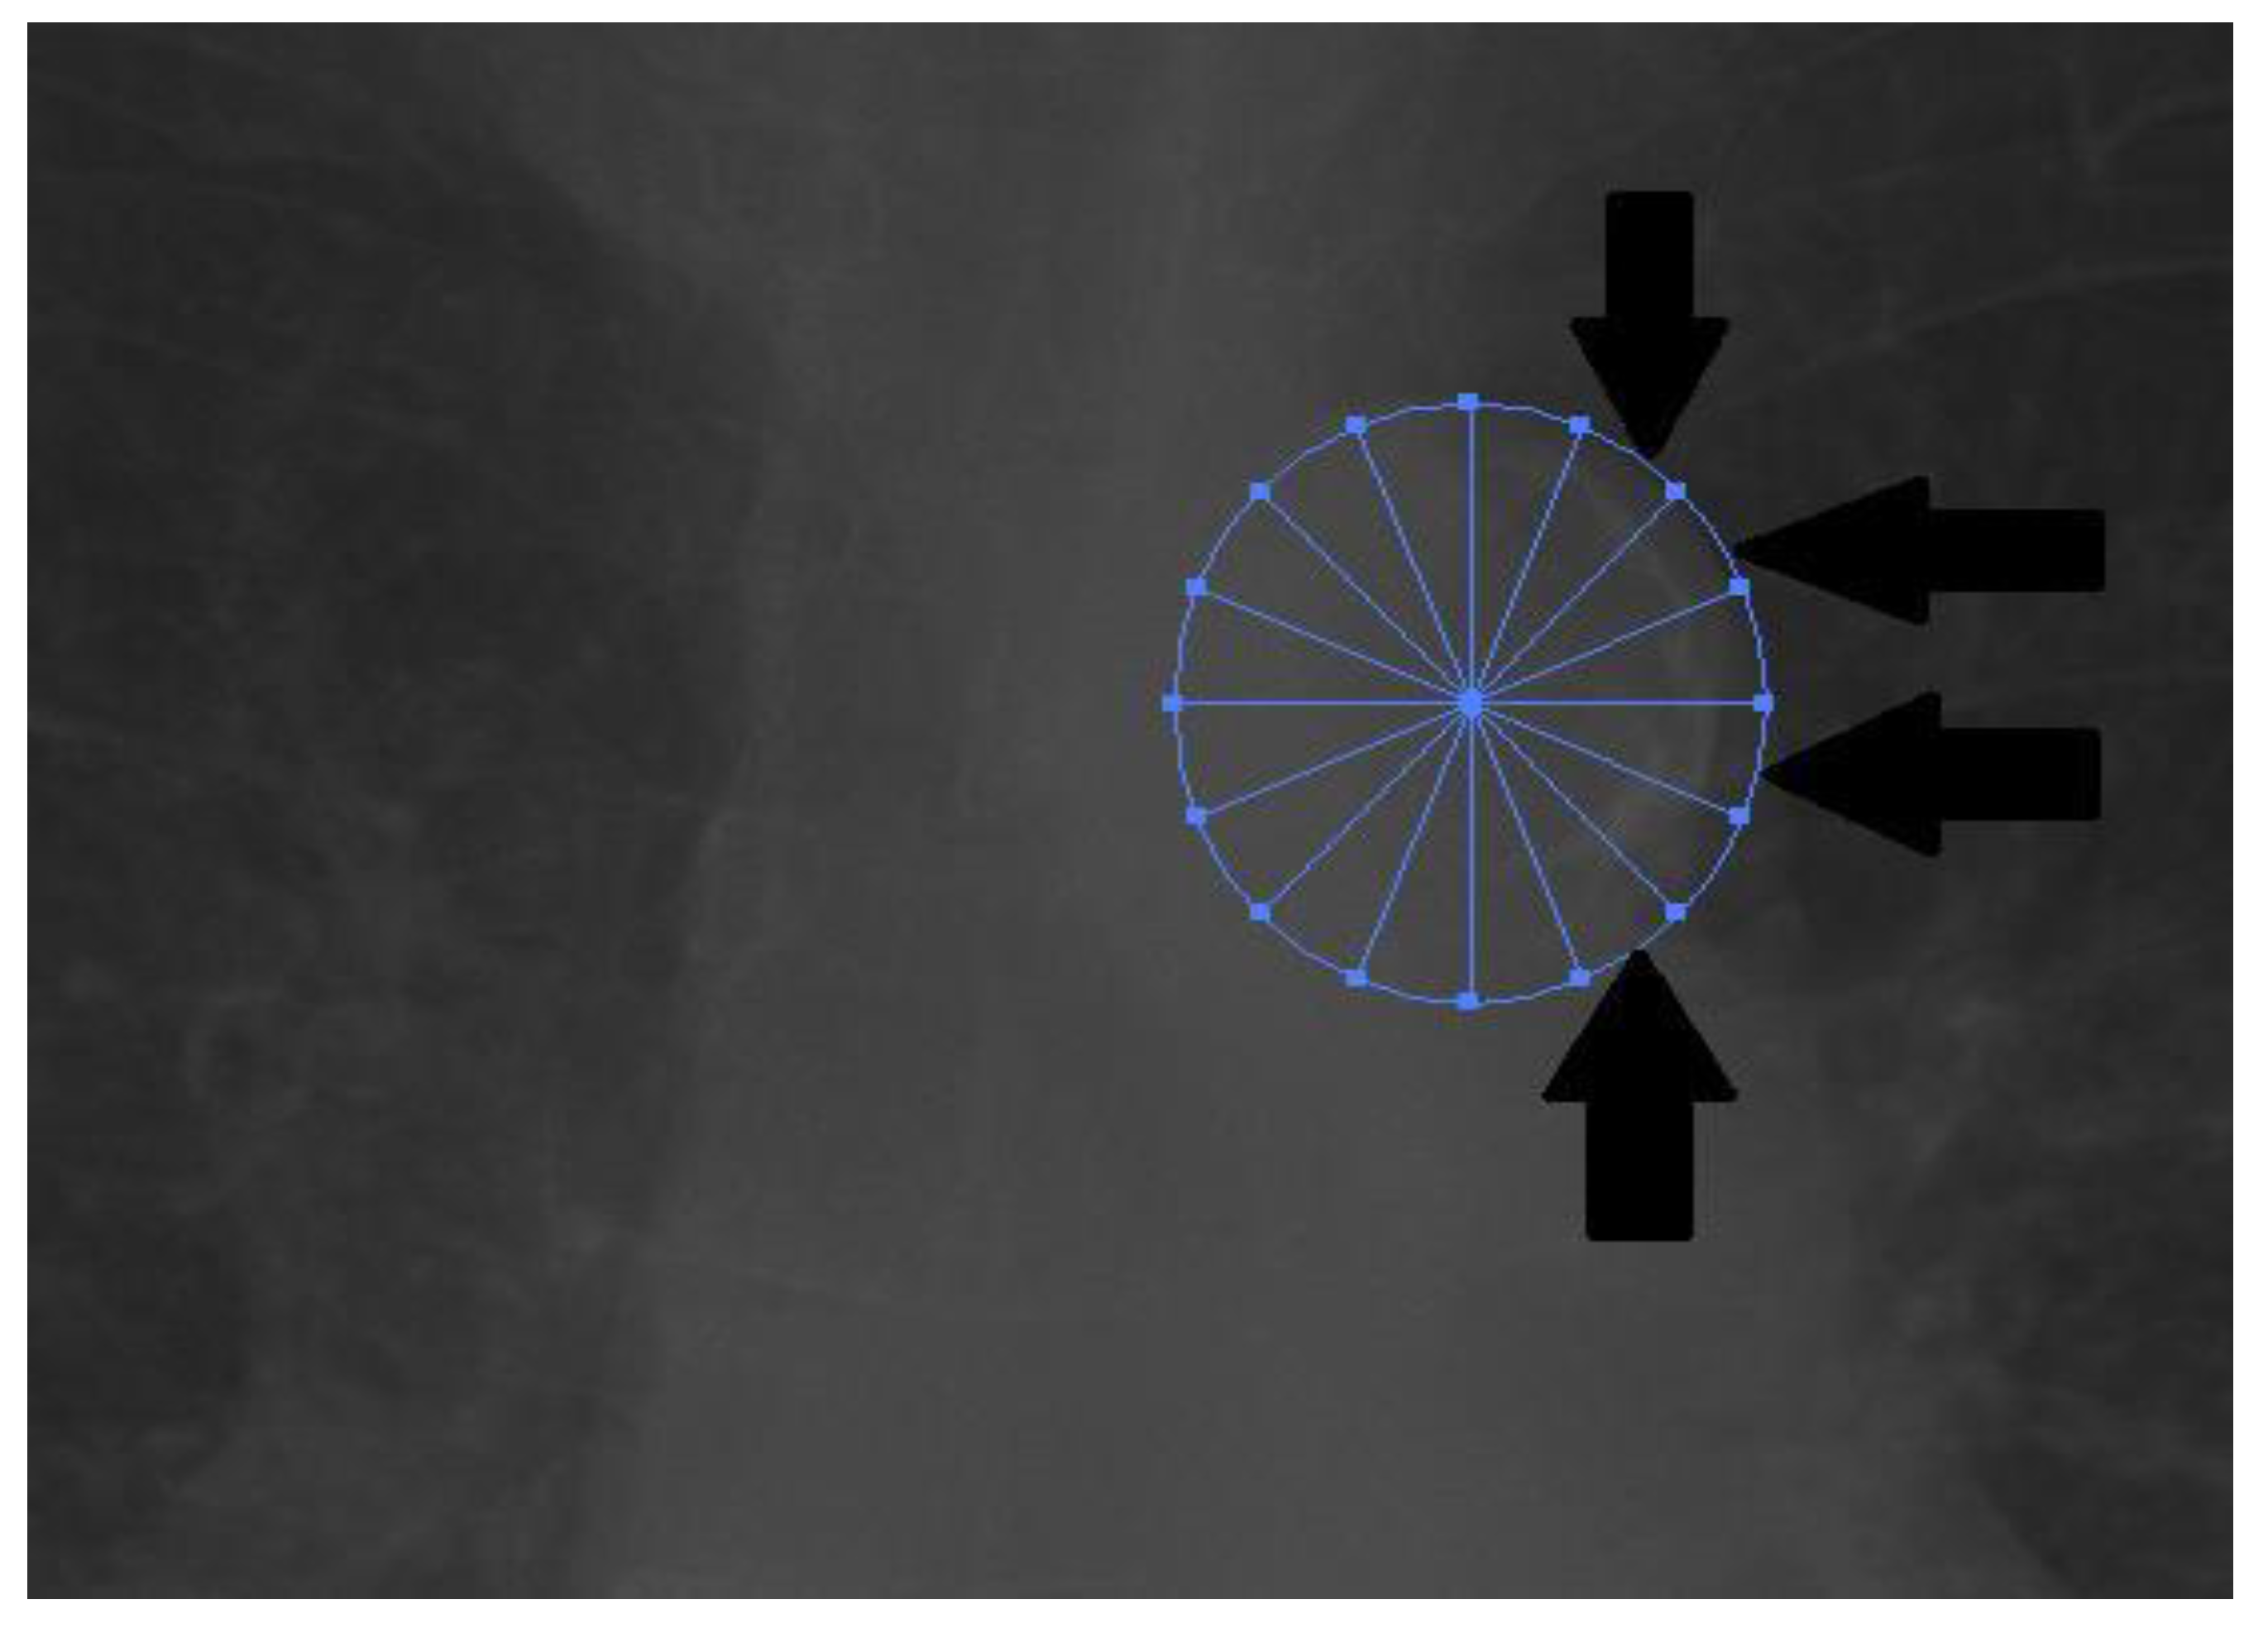

2.2. Measurement

- Ogawa, T.; Ishida, H.; Matsuda, N.; Fujiu, A.; Matsuda, A.; Ito, K.; Ando, Y.; Nitta, K. Simple evaluation of aortic arch calcification by chest radiography in hemodialysis patients. Hemodial. Int. 2009, 13, 301–306. [Google Scholar] [CrossRef] [PubMed]

- Hashimoto, H.; Iijima, K.; Hashimoto, M.; Son, B.K.; Ota, H.; Ogawa, S.; Eto, M.; Akishita, M.; Ouchi, Y. Validity and usefulness of aortic arch calcification in chest X-ray. J. Atheroscler. Thromb. 2009, 16, 256–264. [Google Scholar] [CrossRef] [PubMed]